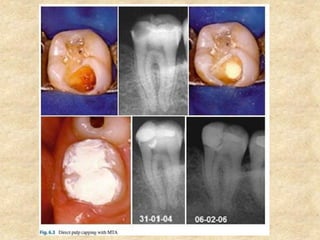

1. Pulp Capping:

• MTA has been proposed as a potential medicament for capping of pulps

with reversible pulpitis because of its excellent tissue compatibility. It is

much superior to the routinely used calcium hydroxide based on the tissue

reaction and the amount and type of dentin bridge formed.

• Calcium hydroxide is associated with tissue necrosis and inflammation

during the initial period of placement but no such inflammation or

necrosis was seen in the pulp tissue adjacent to MTA.

• With MTA, dentin bridge after pulp capping was seen at about 1 week

which steadily increased in length and thickness within 3 months of

capping whereas following pulp capping with calcium hydroxide, the dentin

bridge was less consistent and had numerous tunnel defects.

• Since there is no pulpal necrosis, pulp tissue heals faster with MTA.

Aeinehchi et al in 2003 reported a 0.28 mm thick dentin bridge by 2

months which increased to 0.43 mm by 6 months. The dentin bridge

formed with calcium hydroxide was only 0.15 mm by 6 months.